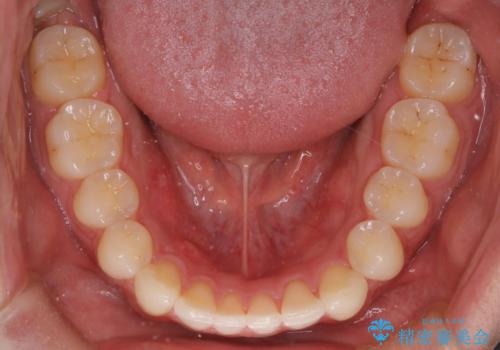

初診時の歯並びの状態としては、上下ともに前歯部の中等度以上のがたつき(叢生)があり、右の前歯が1本飛び出した状態でした。

抜歯は行わず上下顎ともに、主に歯列弓の拡大とディスキング(歯と歯の間に隙間を作る処置)を行い叢生を改善しました。